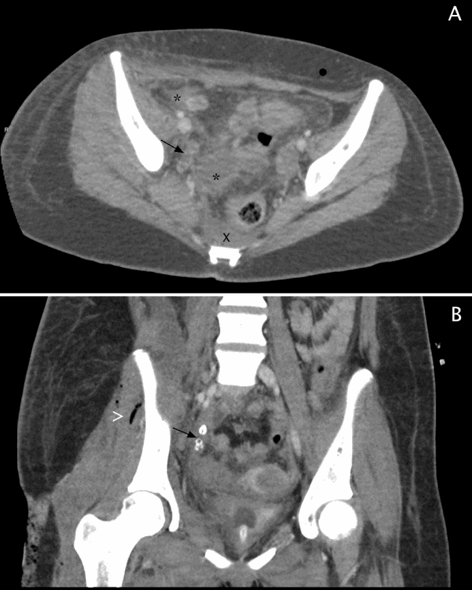

A 16-year-old female was admitted to our children's hospital for intractable right lower extremity pain, edema, fever, elevated white blood count, and elevated serum creatinine kinase. The patient reported a 2-week history of pain that began in the mid abdomen and migrated to the lower extremity. Bedside ultrasound was remarkable for diffuse thigh cellulitis and fluid collections. Emergent magnetic resonance imaging (MRI) was performed demonstrating multi-loculated thigh abscesses, with profound muscle and soft tissue inflammatory changes extending from the femoral canal to the knee (Figure 1A, 1B). In the operating room, a 27-cm medial thigh incision drained 400 cc of foul-smelling purulent drainage from a collection extending from the anterior hip capsule to the knee. Gram stains and culture indicated Escherichia coli (E. coli). There was significant tissue and fascial inflammation with necrosis of the sartorius, pectineus, and adductor magnus, longus, and brevis muscles, necessitating extensive debridement. Following irrigation and debridement, a vacuum assisted wound closure device was placed over the medial thigh. Calf swelling noted during surgery, prompted MRI of the calf demonstrating inflammation and fluid. (Figure 1C, 1D). On hospital day 2, surgery for additional washout yielded additional foul-smelling necrotic tissue from the thigh, necessitating a 37-cm right lateral thigh incision with irrigation and debridement. Lower leg fasciotomy with a 17-cm right lateral incision and a 15-cm medial leg incision exposed all four compartments, with additional purulent drainage. Medial and lateral vacuum assisted wound closure devices were placed on the thigh and leg. Following washout, abdominal and pelvic computed tomography (CT) was obtained to evaluate the abdomen and pelvis. CT showed a dilated appendix with appendicoliths and multiple pelvic abscesses from ruptured appendicitis (Figure 2). Interventional radiology placed a 10 French right lower quadrant drain, obtaining 20 cc of purulent drainage, likewise growing E. coli on culture. Her sepsis progressed, requiring inotropic support with epinephrine and norepinephrine. On day 3, patient was evaluated for appendectomy. She was considered too unstable for laparotomy, therefore, using an extraperitoneal approach, a 10-cm flank incision surgically drained a right iliopsoas abscess. Three separate extraperitoneal Penrose drains (1-inch) were then placed in the retrorenal area, through the femoral triangle, and in the subcutaneous tissue.

Figure 1. MRI imaging. Right thigh (A) axial and (B) sagittal STIR weighted images demonstrate multiloculated abscesses in the posterior thigh, inflammation of the adductor magnus, adductor longus, sartorius, gracilis, semimembranosus and vastus medialis. There is diffuse soft tissue edema. MRI of the right calf sagittal (C) upper calf and (D) lower calf STIR-weighted images demonstrate extensive subcutaneous and muscular edema. There is fluid within the crural fascia.